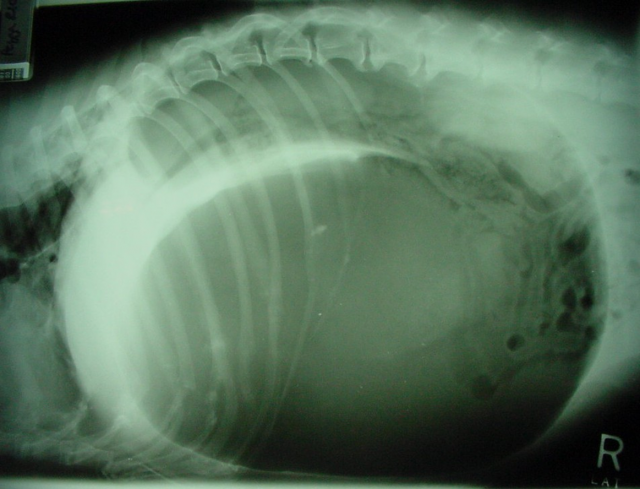

犬胃扭转X线片 |

资源描述:胃内气体形成的阴影被幽门和胃底软组织形成的“支架”分隔(双泡征),这个“支架”呈“C”形,是由折叠的幽门窦壁形成。

文件来源:Ronald S. Walton DVM

右侧卧的X线检查可显示胃膨大、扩张、充满气体的阴影,幽门位于背侧向前接近胃底,胃内气体形成的阴影常被分成条块状,或见阴影被幽门和胃底软组织形成的“支架”分隔(双泡征)。这个“支架”有时呈“C”形,是由折叠的幽门窦壁形成。

如果胃壁内出现气体阴影,提示胃壁组织损伤;如果游离气体出现在腹腔,提示已出现胃破裂。